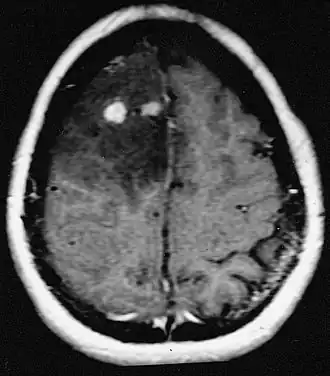

Les métastases cérébrales sont les néoplasmes intracrâniens les plus courants chez les adultes, étant dix fois plus fréquents que les tumeurs cérébrales primaires. Ils marchent à 20 jusqu'à 40 pour cent des adultes atteints de cancer et sont principalement associés au cancer du poumon et du sein et au mélanome . Ces lésions résultent de la propagation des cellules cancéreuses dans la circulation sanguine et surviennent le plus souvent à la jonction de la matière grise et blanche, où la section transversale des vaisseaux sanguins change, emprisonnant les embolies de cellules tumorales . 80 % des lésions surviennent dans les hémisphères cérébraux, 15 pour cent dans le cervelet et 5 pour cent dans le tronc cérébral. Environ 80 % des patients ont des antécédents de cancer systémique et 70 pour cent ont de multiples métastases cérébrales.

Des progrès significatifs ont récemment été réalisés dans le diagnostic et le traitement de ces lésions, entraînant une amélioration de la survie et du contrôle des symptômes. L'apparition des signes et des symptômes est similaire à celle d'autres lésions massives du cerveau. La méthode de diagnostic de choix est l'imagerie par résonance magnétique utilisant des produits de contraste.